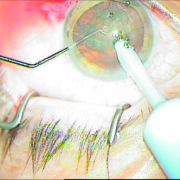

H επιστημονική μας ομάδα έχει την ικανότητα αντιμετώπισης όλων των τύπων των καταρρακτών, απλών, με μικρή κόρη, υπερώριμων, με φακοδόνηση, μετά από Laser μυωπίας και υπερμετρωπίας, καθώς και σοβαρότερων επιλεγμένων περιπτώσεων.

Οι σύγχρονες μικροχειρουργικές τεχνικές αποβλέπουν στον ελάχιστο τραυματισμό του οφθαλμού και στην τοποθέτηση του τεχνητού ενδοφακού στην φυσική του θέση που είναι ο οπίσθιος θάλαμος. Οι ασθενείς απολαμβάνουν τα πλεονεκτήματα των επεμβάσεων μικρής τομής χωρίς ράμματα, με άμεση αποκατάσταση της όρασης και χωρίς μετεγχειρητικό αστιγματισμό.